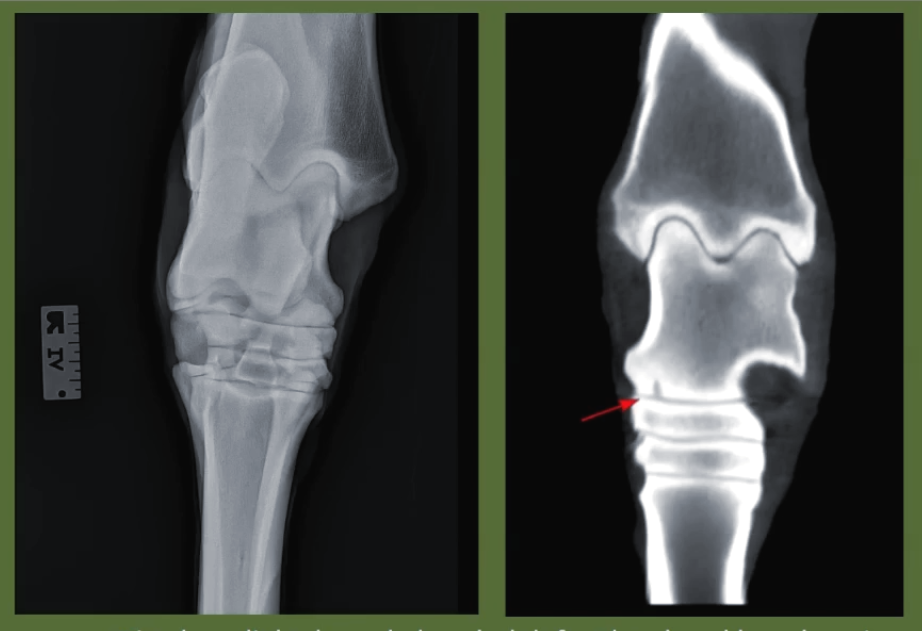

Image Gallery

Case Studies